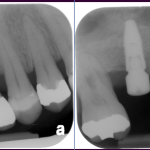

The bone used in a sinus lift may come from your own body (autogenous bone), from a cadaver (allogeneic bone) or from cow bone (xenograft). You will need X-rays taken before your sinus lift so the dentist can study the anatomy of your jaw and sinus. You also may need a special type of computed tomography (CBCT) scan. This scan will allow the dentist to accurately measure the height and width of your existing bone and to evaluate the health of your sinus.

After several months of healing, the bone becomes part of the patient’s jaw and dental implants can be inserted and stabilized in this new sinus bone.

If enough bone between the upper jaw ridge and the bottom of the sinus is available to stabilize the implant well, sinus augmentations and implant placement can sometimes be performed as a single procedure. If not enough bone is available, the sinus augmentation will have to be performed first, then the graft will have to mature for several months, depending upon the type of graft material used. Once the graft has matured, the implants can be placed.